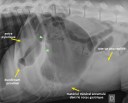

Corps étranger 1 – Réponse

22 avril 2012